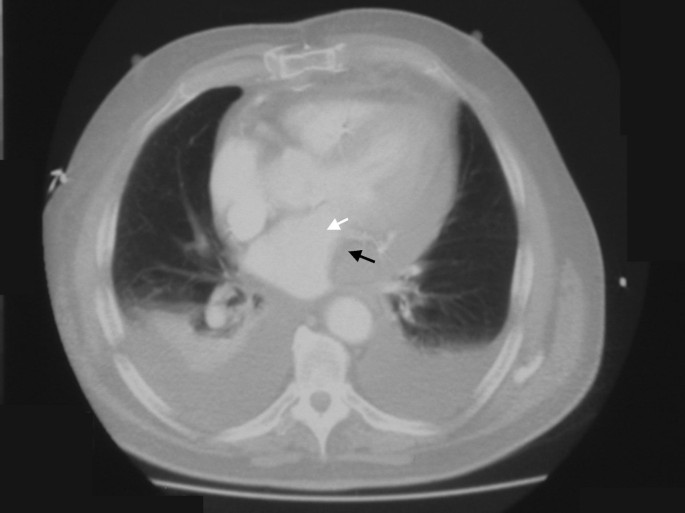

A TTE was performed by an experienced sonographer which showed similar left ventricular function as before and no evidence of pericardial collection or tamponade. In view of depressed LV function, 0.05 mcg/kg/min of adrenaline infusion was commenced and an intra-aortic balloon pump (IABP) was inserted in the right common femoral artery. Despite these measures, the CI index improved only to 2.0 litres/min/m2. By this stage, the CVP was 16 mmHg, the serum lactate increased from 1.0 to 4.1 and the urine output was 30 mls/hr. Despite a normal TTE, a strong suspicion of pericardial tamponade was made. A trans-oesophageal echocardiogram (TOE) was not available and it was decided to perform a CT scan of the chest (without contrast). A Siemens SOMATOM Sensation 16 slice CT scanner (Siemens Medical Solutions Inc, PA, USA) was used. Figure [1] shows a localised 4 cm pericardial collection (black arrow) around the free wall of the left ventricle (white arrow) causing tamponade. Surgical exploration was contemplated. On removal of the wires at reopening, blood was released from the pericardium with pressure and large amount of clots were removed from around the LV. Thereafter, the BP improved to 125/85 mmHg with a CI of 4.3 litres/min/m2. The IABP was removed after 24 hours and the inotropes were weaned off. Thereafter, the patient made an unremarkable recovery and was discharged home on day 7.